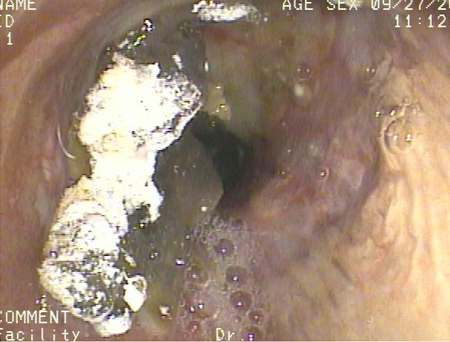

Acute aspiration

Bronchoscopy showing barium aspiration in a lung transplant patient in the right mainstem bronchus after a barium swallow study

From the collection of Dr Kamran Mahmood